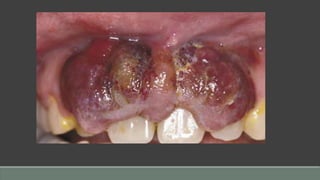

Kaposi’s Sarcoma

Clinical Presentation

• Classic form associated with slow but pernicious growth over many years; oral lesions rarely seen

• Endemic form more rapid; oral lesions rarely seen

• AIDS-associated KS most commonly seen on keratinized mucosa/mucoperiosteal tissues; strong

predilection for hard palate, followed by gingiva, buccal mucosa, and tongue (prevalence decreasing

with treatment for AIDS)

• Evolution from bluish macule to nodule(s)

• Evolution to multiple lesions

• May precede or follow cutaneous lesions

• Usually asymptomatic